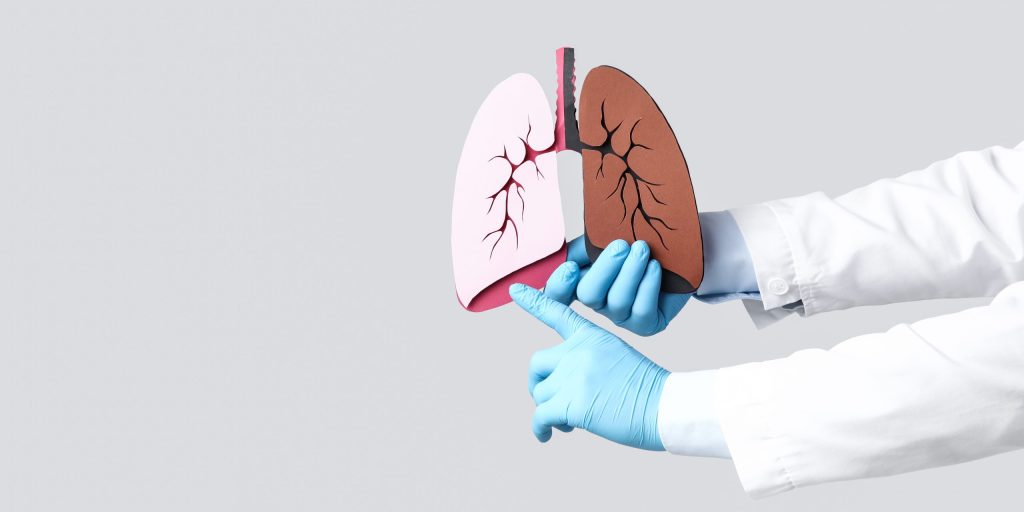

Tobaksrygning og vaping er undervurderede årsager til interstitielle lungesygdomme. De rygerelaterede interstitielle lungesygdomme spænder fra milde bronkiolære forandringer til akut toksisk lungeskade og kronisk fibrose. Diagnosen beror på en grundig ekspositionsanamnese, billeddiagnostik samt lungefunktion. Tidlig genkendelse og konsekvent eksponeringsophør er afgørende for prognosen.